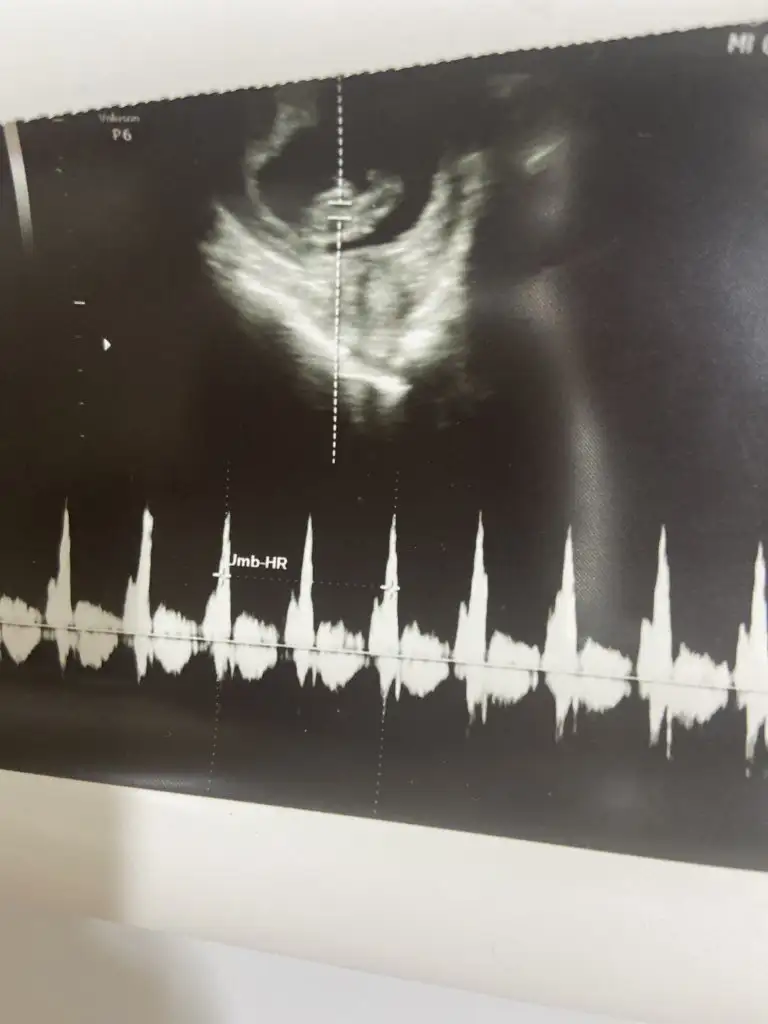

Rahim ağzı uzunluğuna baktı normal iyi dedi.

3.5 santim dedi.